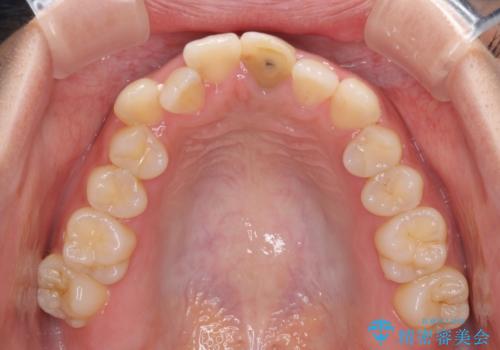

前歯のクロスバイトと変色した歯 ワイヤー矯正とセラミック治療

- 前歯のクロスバイトと神経を取り除いた後に変色してしまった前歯を気にして来院された患者様です。

変色してしまった前歯は、反対側の歯と比べて歯肉が覆い被さっていたため、骨整形を含めた歯周外科処置を行い、歯肉ラインを整えることとしました。